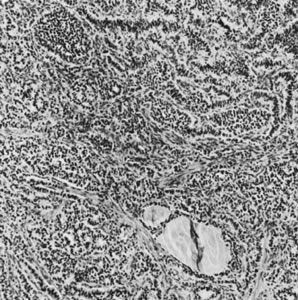

On microscopic examination, the granulosa cell tumor can be divided into two major subtypes, adult form and juvenile form, which differ strikingly in their patterns and cytologic features. The adult granulosa cell tumor is occasionally composed almost entirely of granulosa cells, with few or no accompanying thecal or fibroblastic elements, but more often the latter are present in some amount and may be substantial. The granulosa cell component of the tumor has a variety of patterns. The well-differentiated form most commonly has a microfollicular (Fig. 2), trabecular (Fig. 3), or insular pattern, or a combination of the three. Rarely, the pattern is macrofollicular, with the tumor composed of large follicles resembling normally developing follicles. Less well-differentiated tumors typically have a diffuse or sarcomatoid pattern, characterized by a sea of cells with little or no intervening stroma (Fig. 4); this type of tumor is particularly apt to rupture. Sometimes a watered-silk or zigzag (gyriform) pattern is seen. The stromal element of the tumor may consist of fibroblasts that have laid down considerable collagen, as well as cells that resemble theca externa, theca interna, or theca lutein cells.

Fig. 2. Granulosa cell tumor, microfollicular pattern with Call-Exner bodies (magnification, ×290).(Scully RE, Morris JM: Functioning ovarian tumors. In Meigs JV, Sturgis SH [eds]: Progress in Gynecology, Vol 3. New York, Grune & Siralton, 1957, by permission.)